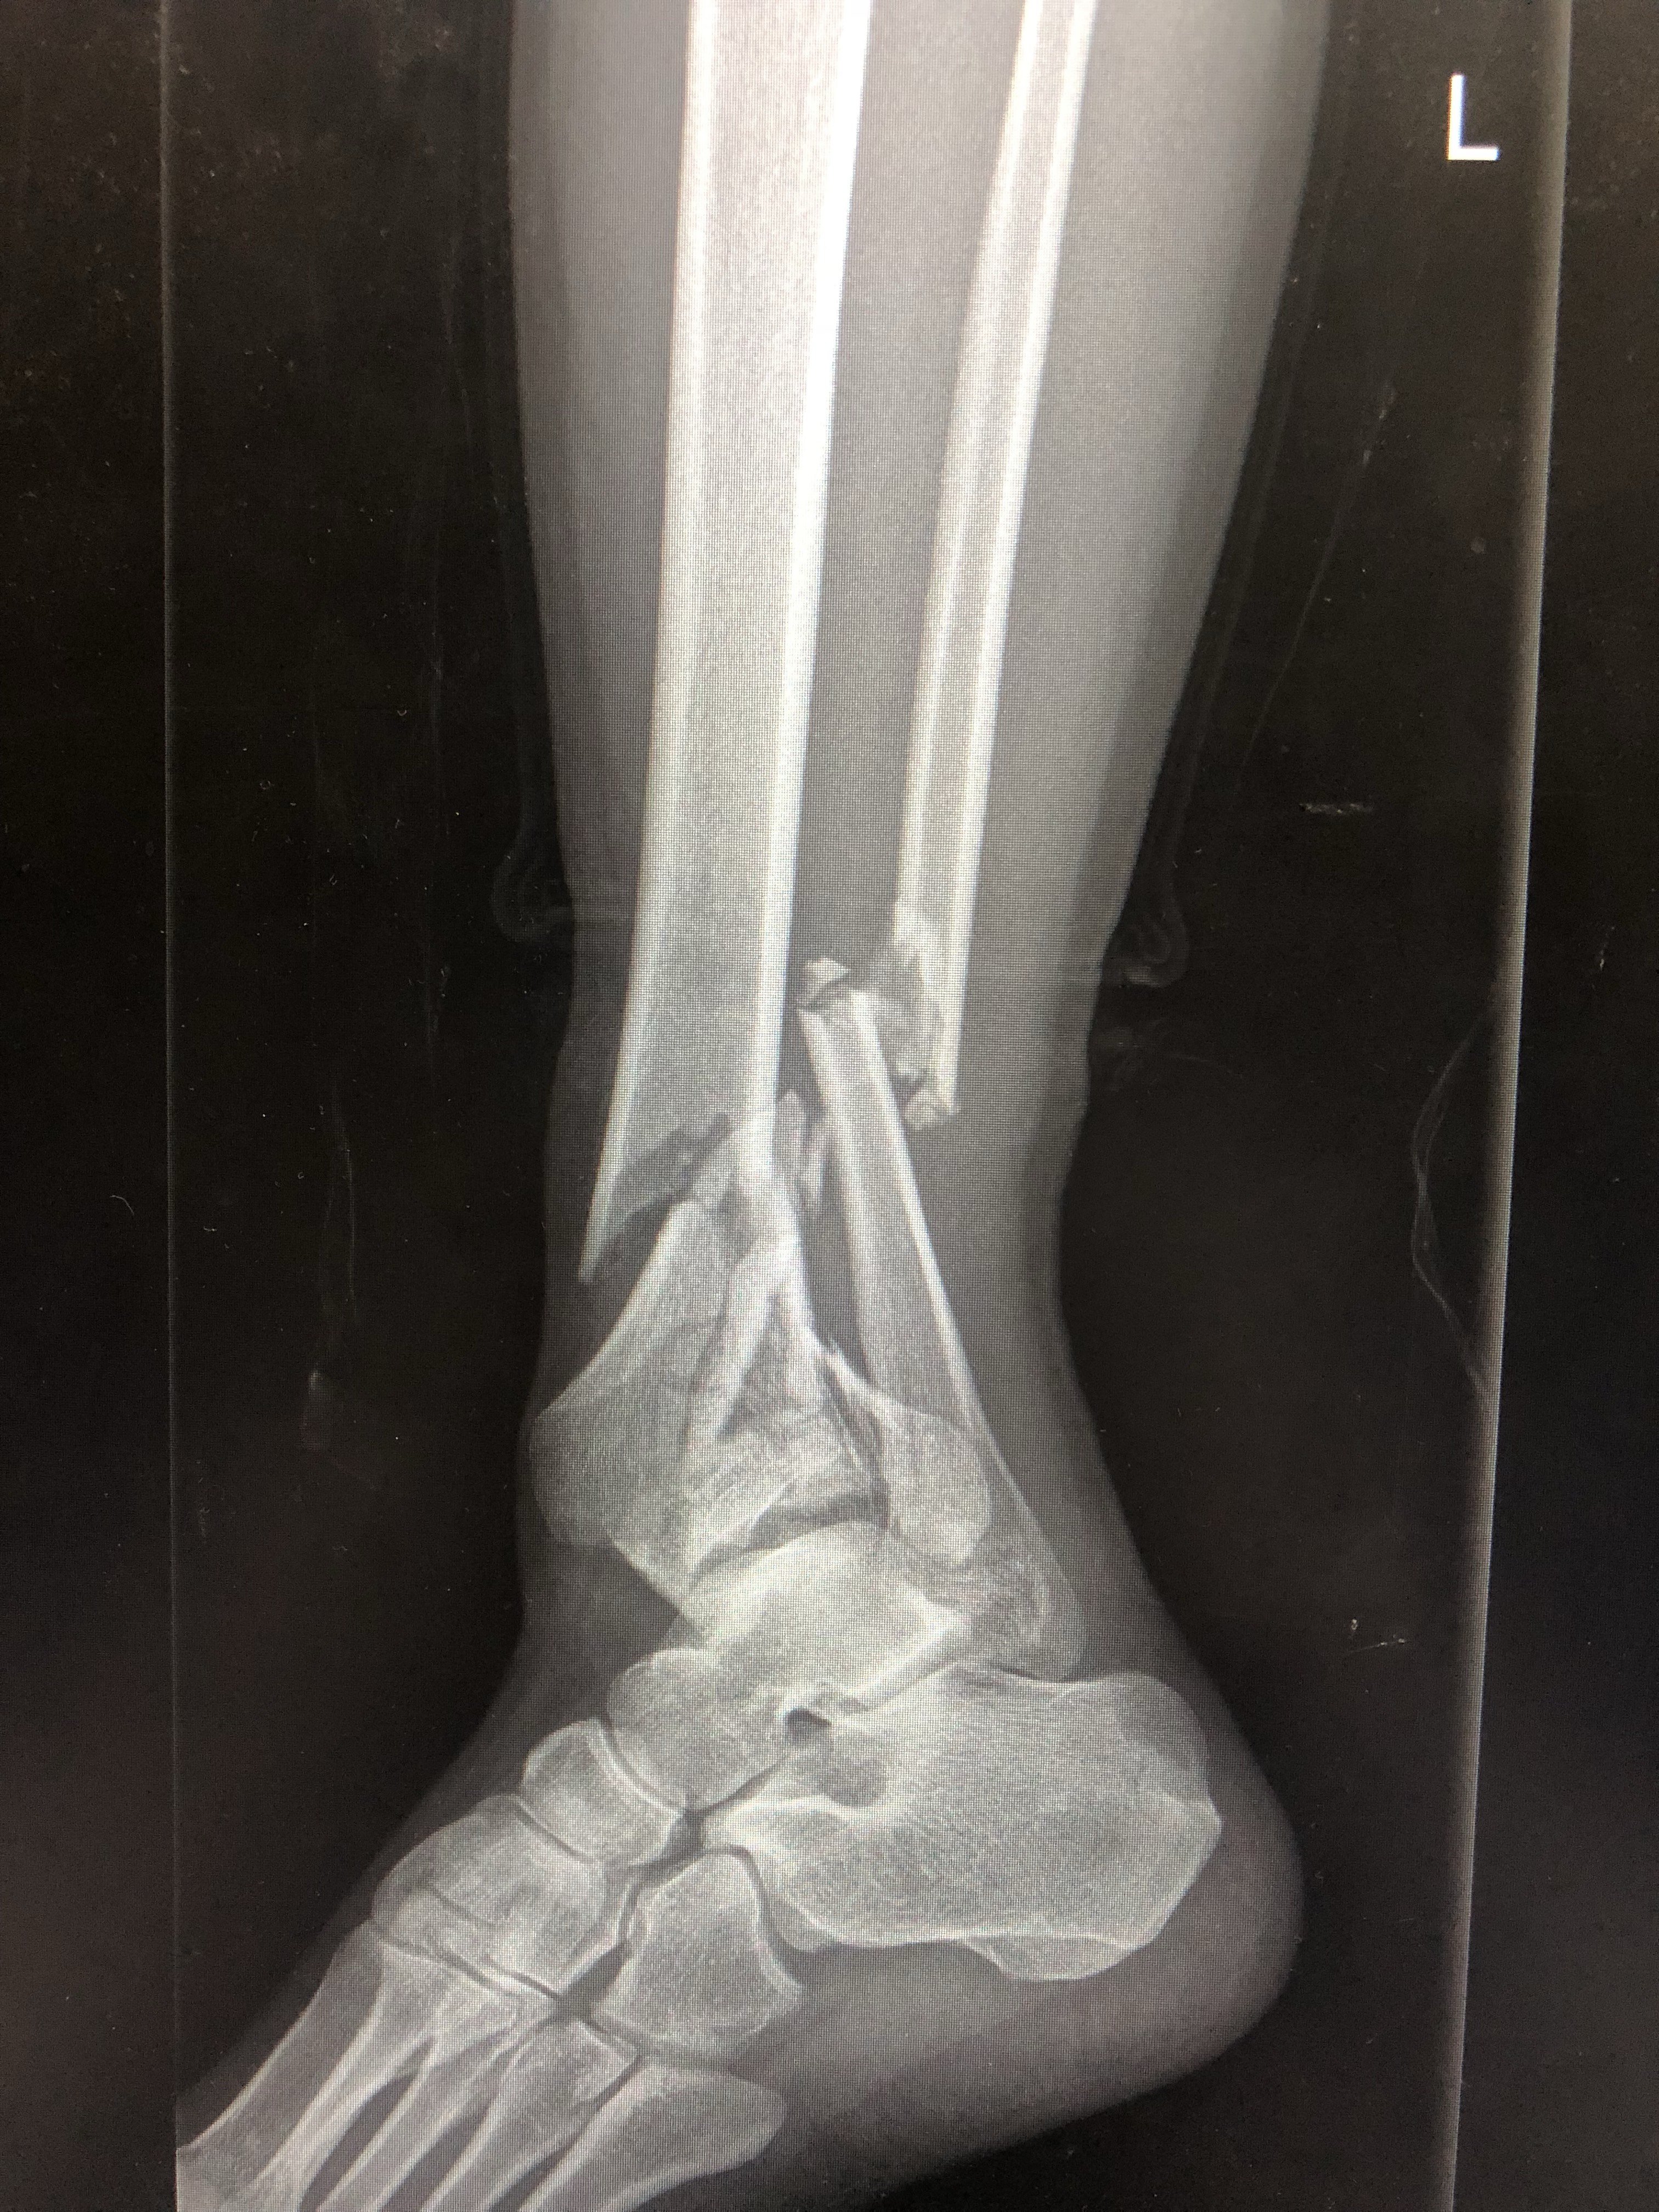

左腓骨骨折 X线影像 医学影像 医学图谱 37度医学网